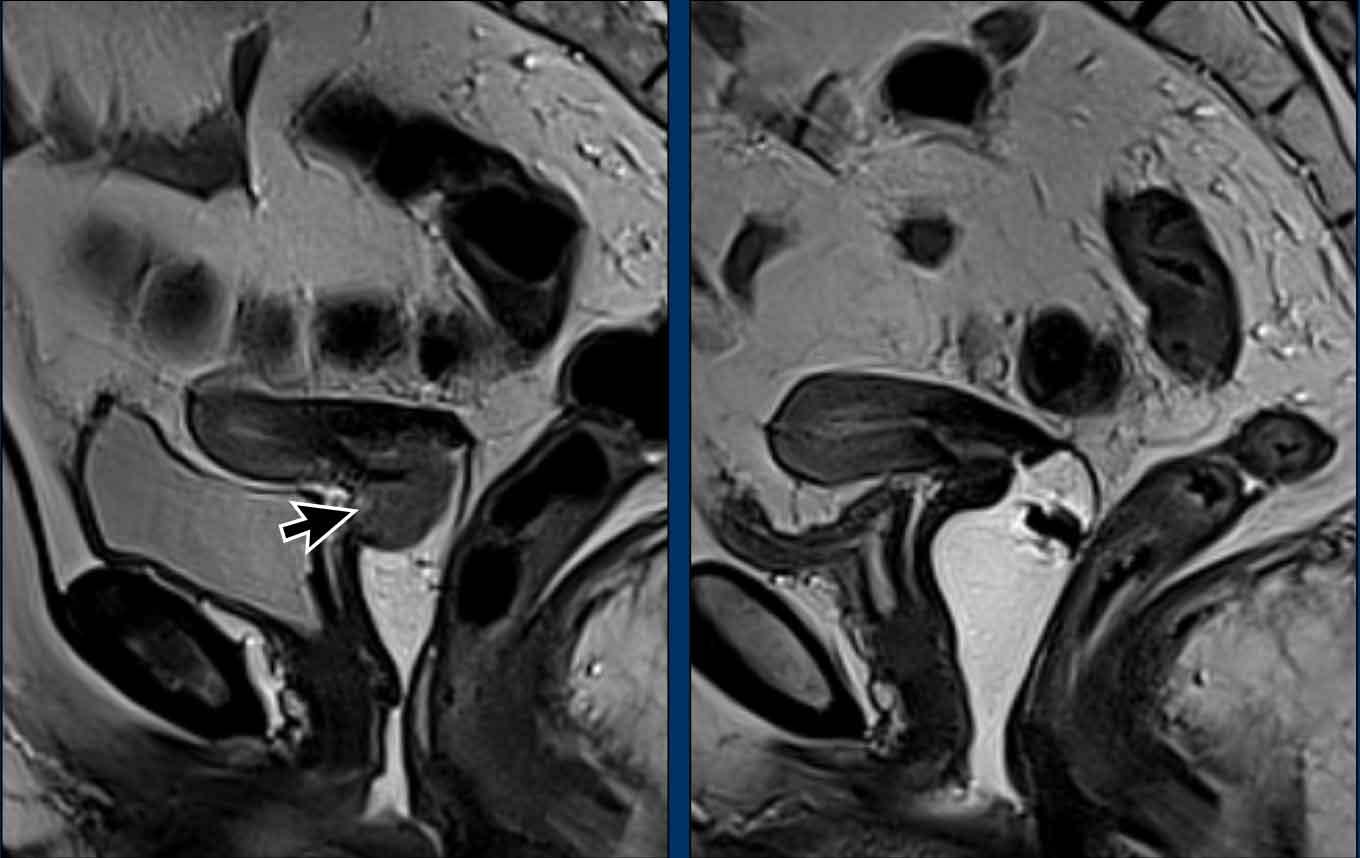

Lưu ý: các biến thể giải phẫu cổ tử cung

Cần tính đến vị trí của ống cổ tử cung và lập kế hoạch các chuỗi xung MRI vuông góc và song song tương ứng.

Ví dụ minh họa cách góc gập và đặc biệt là hướng nghiêng ảnh hưởng đến việc lập kế hoạch chuỗi xung.

Trong trường hợp này, cổ tử cung ở tư thế nghiêng trước (anteversion) và thân tử cung ở tư thế gập sau (retroflexion).

Cần nhớ rằng trong ung thư cổ tử cung, các chuỗi xung axial được lập kế hoạch vuông góc với ống cổ tử cung.

Một ví dụ khác cho thấy cổ tử cung ở tư thế nghiêng sau (retroversion) và thân tử cung ở tư thế gập trước (anteflexion).

Quan sát cách biến thể tư thế này ảnh hưởng đến việc lập kế hoạch chuỗi xung tương ứng.